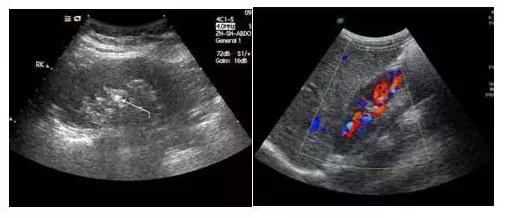

首先,黑白超和彩超并不是在影像的颜色上有区别,许多人认为彩超和黑白超的区别就是彩色电视机和黑白电视机的区别,其实不然,彩超显示的图像也是黑白的。

它们的区别是黑白超用灰度调制显示声束扫描人体切面的声像图;彩超则是在黑白超的基础上,增加了血流信号的处理,一般用红、蓝、绿三种基本颜色,呈现出检查区域的血管分布、血流方向、血流速度等